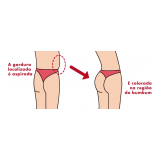

Lipoaspiração a Laser

Você merece a qualidade e comprometimento entregues pela equipe deste consultório médico e se neste momento está à procura de uma equipe que realize lipoaspiração a laser saiba que a FF Cirurgia Plástica disponibiliza de imediato este serviço para você!

Lipoaspiração a laser: atendimento eficiente e com qualidade que você sempre buscou!

Neste consultório médico você encontrará profissionais eficientes e com experiência de excelência. Usufrua de bom atendimento, através dos melhores preços do mercado e de assistência especializada sempre à sua disposição! Leve as suas dúvidas, converse com a equipe da FF Cirurgia Plástica. Contrate bons serviços e sinta-se mais seguro para cuidar da saúde.